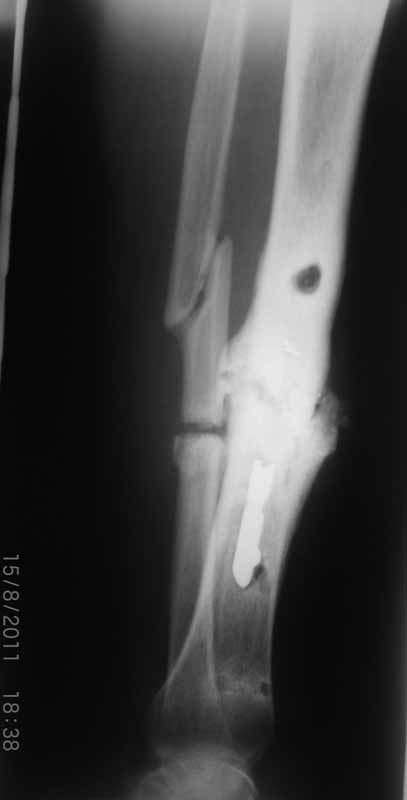

Первично у пациента травма в марте 2009г, когда в результате ДТП получил открытый оскольчатый перелом обеих костей правой голени на границе средней и нижней трети. При поступлении - скелетное вытяжение, затем по заживлению раны произведен остеосинтез пластиной. Со временем (точное время сказать затрудняется) пациенту разрешили полную нагрузку на конечность. Через год после операции пластина сломалась, в связи с чем пластина удалена и установлен интрамедуллярный гвоздь. Через 2 месяца разрешили полную нагрузку и гвоздь сломался. В сентябре 2010 произведено наложение спицевого компрессионно-дистракционного аппарата. В мае 2011 появилось отделяемое в местах проведения спиц, в связи с чем аппарат демонтирован. Правая голень временно иммобилизирована гипсовой повязкой, разрешена нагрузка на правую нижнюю конечность. После снятия повязки - клиника ложного сустава обеих костей правой голени. В настоящее время отмечается угловая деформация правой голени на границе средней и нижней трети с отклонением оси в медиальную сторону. Кожные покровы изменены за счет трофических нарушений(имеют более темную окраску по сравнению со здоровой ногой)На коже рубцы на месте проведения спиц.Движения в коленном и голеностопном суставах в полном объеме безболезненны. Пульсация артерий на стопе отчетливая, выпадение чувствительности от третьего луча в латеральную сторону по тылу стопы.  В таком виде пациент оказался у нас. Рады выслушать предложения о тактике лечения.

Имя     : CIMG1118-1.jpg

Url     : http://weborto.net:8080/pipermail/ortho/attachments/20110816/e165342b/attachment-0003.jpg